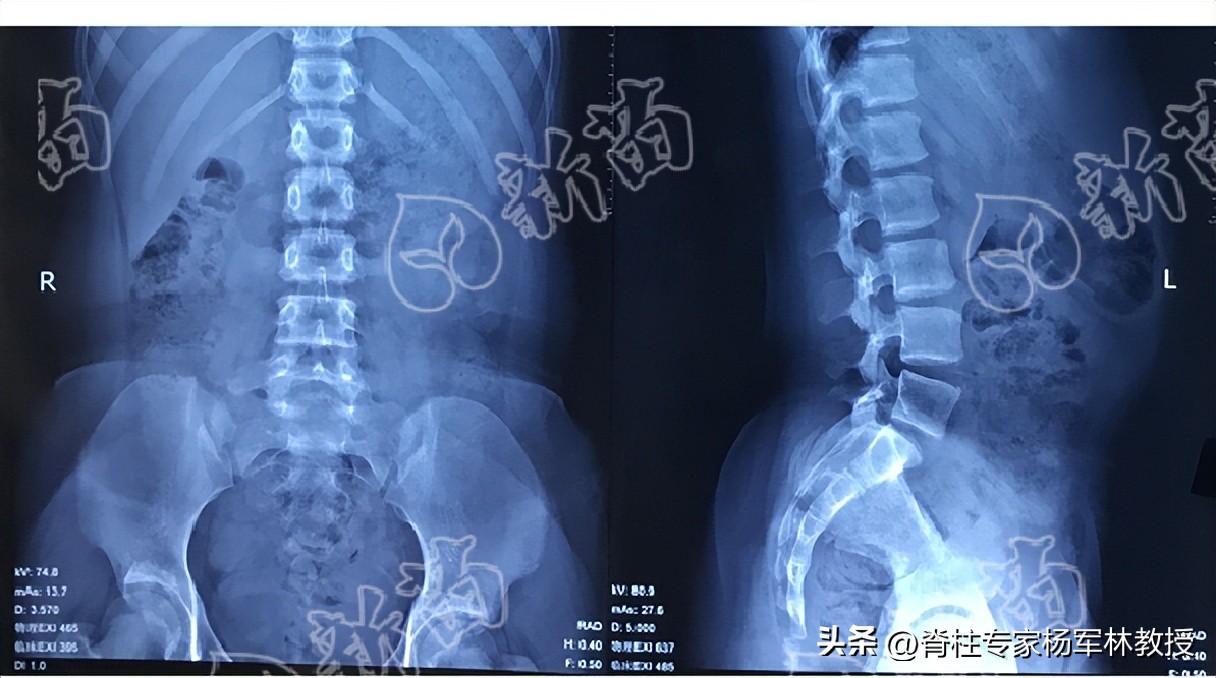

全脊柱X光片正位片和侧位片有何不同?

许多患者在拍片时,为了节省时间和减少辐射,常常忽略掉拍摄全脊柱X光片的侧位片。

全脊柱X光片的正位片能够用以评估脊柱冠状面(即正面)的侧弯严重程度,如脊柱侧弯角度、椎体旋转程度、脊柱弯曲类型,以及是否躯干失衡等。

而全脊柱X光片侧位片则是评估脊柱矢状面(即侧面)的情况,如是否脊柱后凸?是否颈椎反弓?是否腰椎滑脱?是否椎弓峡部裂?是否骨盆前倾或后倾等问题。

图片源自:新苗团队

因此,全脊柱X光片的正位片和侧位片能评估出脊柱的不同问题,必须要拍摄两张。